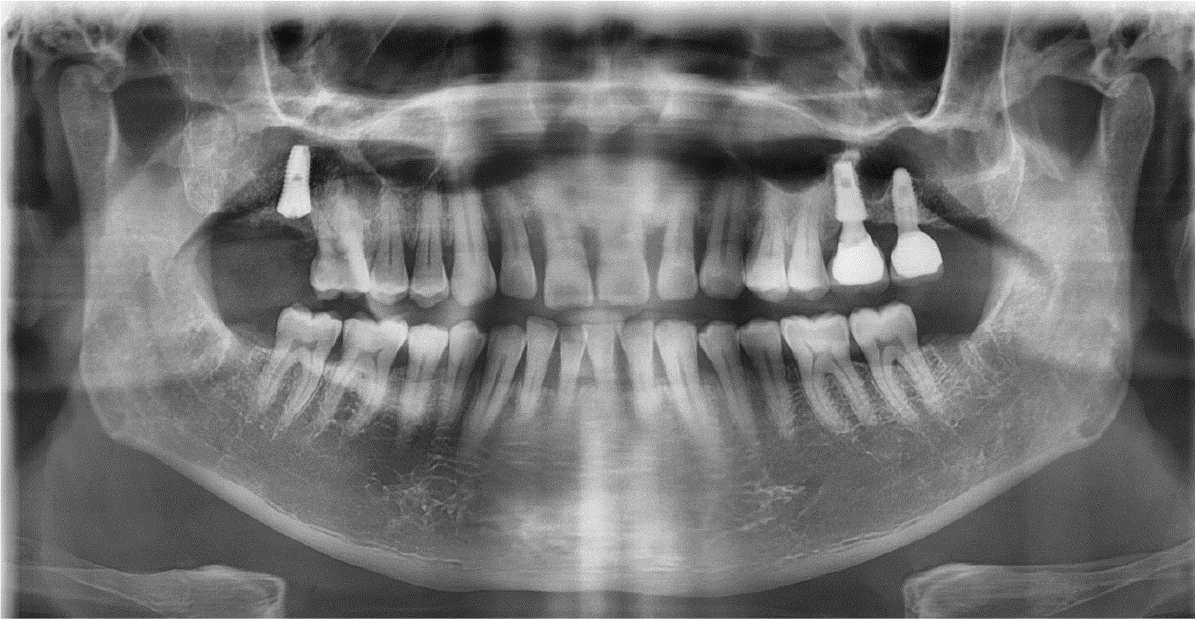

The right maxillary second and third molars were extracted. A lateral bony window was prepared, and the sinus membrane was thoroughly lifted from the sinus floor with bony window lifted upward and inward. But the mesial aspect of the lifted sinus membrane was perforated (about 4 – 5 mm). A collagen wound dressing (Colla-tape®; Zimmer Dental Carlsbad, CA, USA) was used for the repair of the sinus membrane perforation (Fig. 2). Alloplastic bone-grafting material (A-oss®; Osstem implant Co., Seoul, Korea) was packed and the implant placement (Superline®; Dentium implant Co., Seoul, Korea) was performed (Fig. 3). After 7 days, the patient had pain, nasal discharge and foul odor on the right paranasal area. Under local anesthesia, the flap was elevated. The infected bone material, fixture, collagen wound dressing and infected tissue were removed (Fig. 4). Sinus irrigation was performed for about 5 minutes, until the foul odor and the blockage of ostium disappeared. During this procedure, the size of perforation got bigger by about 1 cm.

After the stuffy nose on the right side was completely gone, the bony window was extended anteriorly and the sinus membrane around perforated area was lifted. The perforated membrane was sutured (Rexlon nylon 4-0®; SM eng, Seoul, Korea) and the collagen wound dressing was inserted for the complete sealing (Fig. 5). Alloplastic bone-grafting material (A-oss®; Osstem implant Co., Seoul, Korea) was packed and the implant placement (Superline®; Dentium implant Co., Seoul, Korea) was performed immediately (Fig. 6). After operation, conservative treatment (augmentin 625 mg, acidified pseudo ephedrine HCL 2.5 mg, acetaminophen 500 mg, 3 times daily) continued for 1 week. After one week, the suture was removed and the discomfort symptom was disappeared. After 3 months later, occlusal loading started (Fig. 7). In the 3-months follow-up, the implant and lifted sinus bone formation were stable (Fig. 8). In the 2-years follow-up, the implant was left stable and the sinus lifted bone was maintained well (about 6 mm height) (Fig. 9).